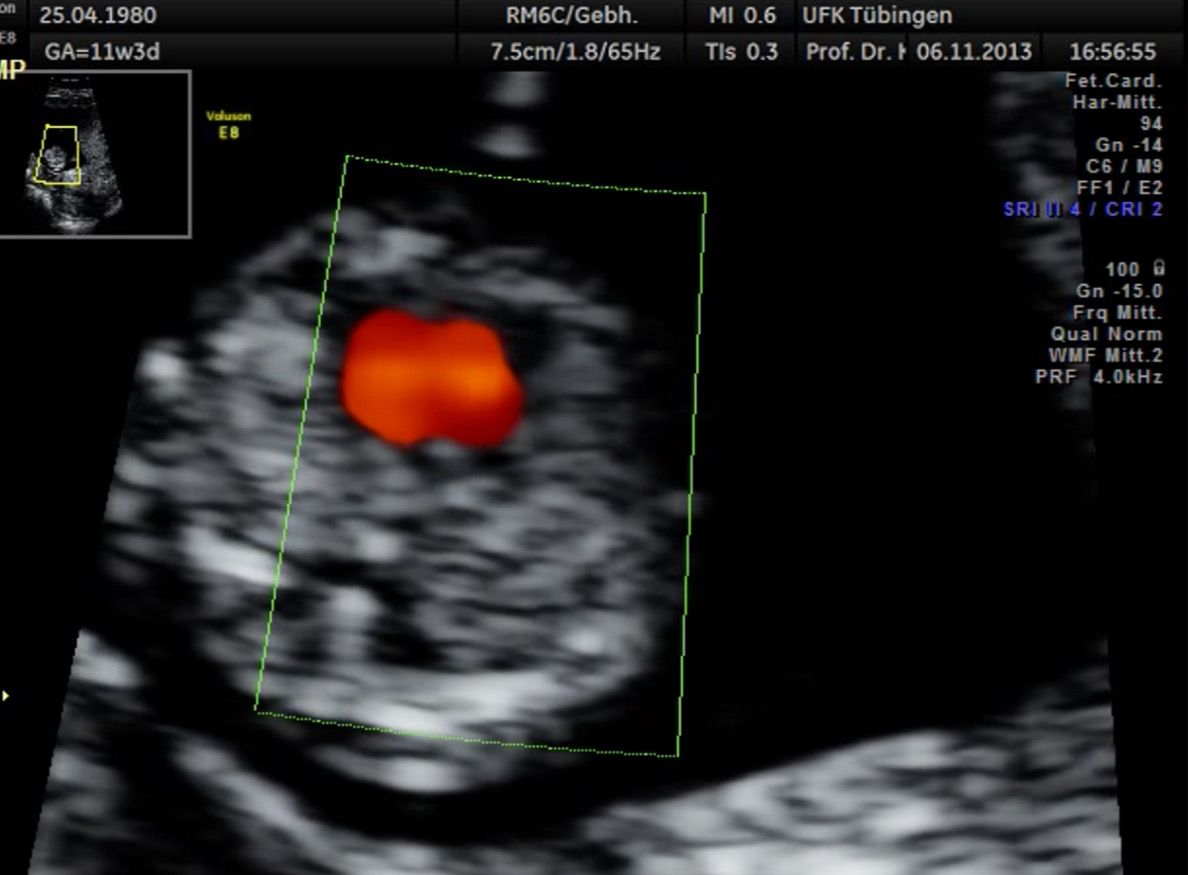

Herz

Das Ergebnis der Ultraschalluntersuchung ist wegweisend. Dabei wird der Fet vermessen, die Organe werden untersucht und die sonographischen Marker zur Risikoberechnung für Chromosomenstörungen werden beurteilt. Das sind: die Nackentransparenzdicke, Nasenbein sowie der Blutfluss in der rechten Herzhälfte und im Ductus venosus, einem Gefäß in der Leber des Feten.